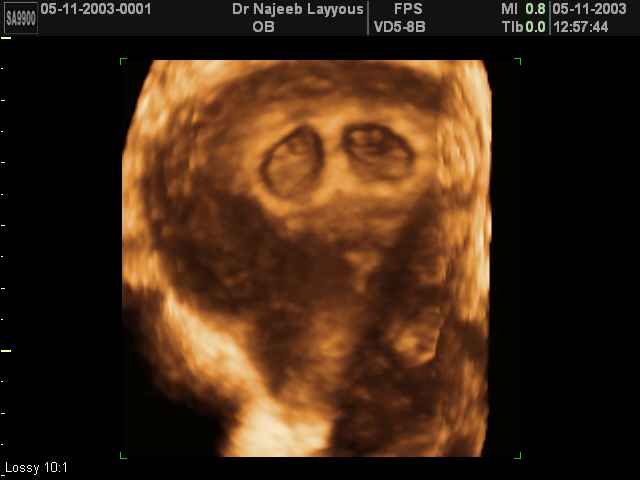

3D Photos échographie de grossesse multiple : Jumeaux, triplés et quadruples| Dr N Layyous

3D Photos échographie de grossesse multiple